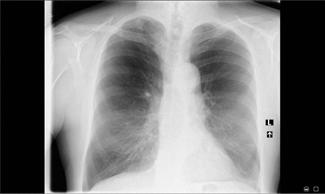

1. RTG klatki piersiowej (r yc. 2.1) – wykazało w prawym środkowym polu płucnym w rzucie przedniego odcinka III żebra, w linii przy mostkowej widoczny nieregularny dobrze wysycony cień o średnicy 8 mm – zmiany włókniste pozapalne (wykluczono proces rozrostowy w dalszej diagnostyce). Poza tym pola płucne bez zmian ognisko wych. Sylwetka serca w granicach normy. Przepona i kąt przepo ‑ nowo żebrowy wolne.